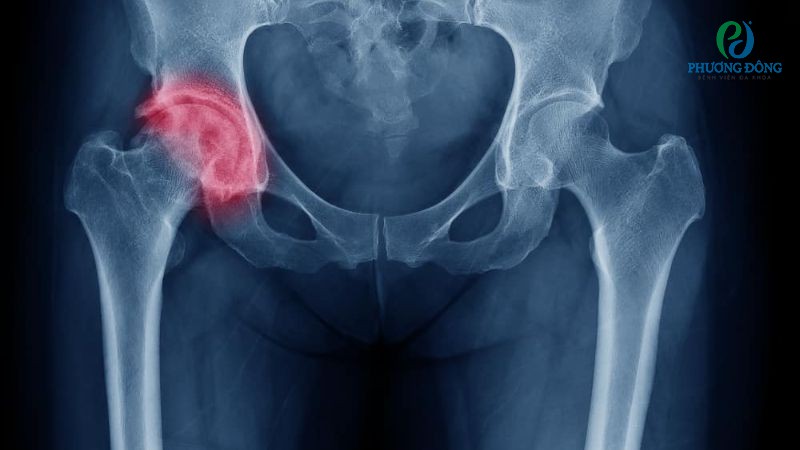

Gãy xương đùi

Gãy xương đùi chủ yếu xảy ra ở phần trên, nơi kết nối với xương chậu để tạo thành khớp háng. Một số dạng chấn thương thường gặp bao gồm gãy chỏm xương đùi, gãy cổ xương đùi và gãy liên mấu chuyển xương đùi.

Tuy xương đùi thuộc nhóm xương chắc khỏe nhất trong cơ thể, nhưng vẫn có thể đứt gãy khi té ngã mạnh hoặc tai nạn giao thông nghiêm trọng. Tỷ lệ chấn thương tăng cao ở nhóm bệnh nhân trên 65 tuổi, phụ nữ mãn kinh do thường đi kèm tình trạng loãng xương.